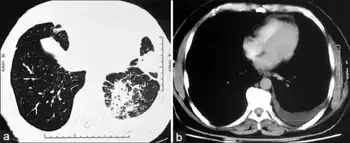

Selective IgM immunodeficiency-a)Show areas of consolidation in inferior segment of lingular lobe b)demonstrate left pleural effusion)